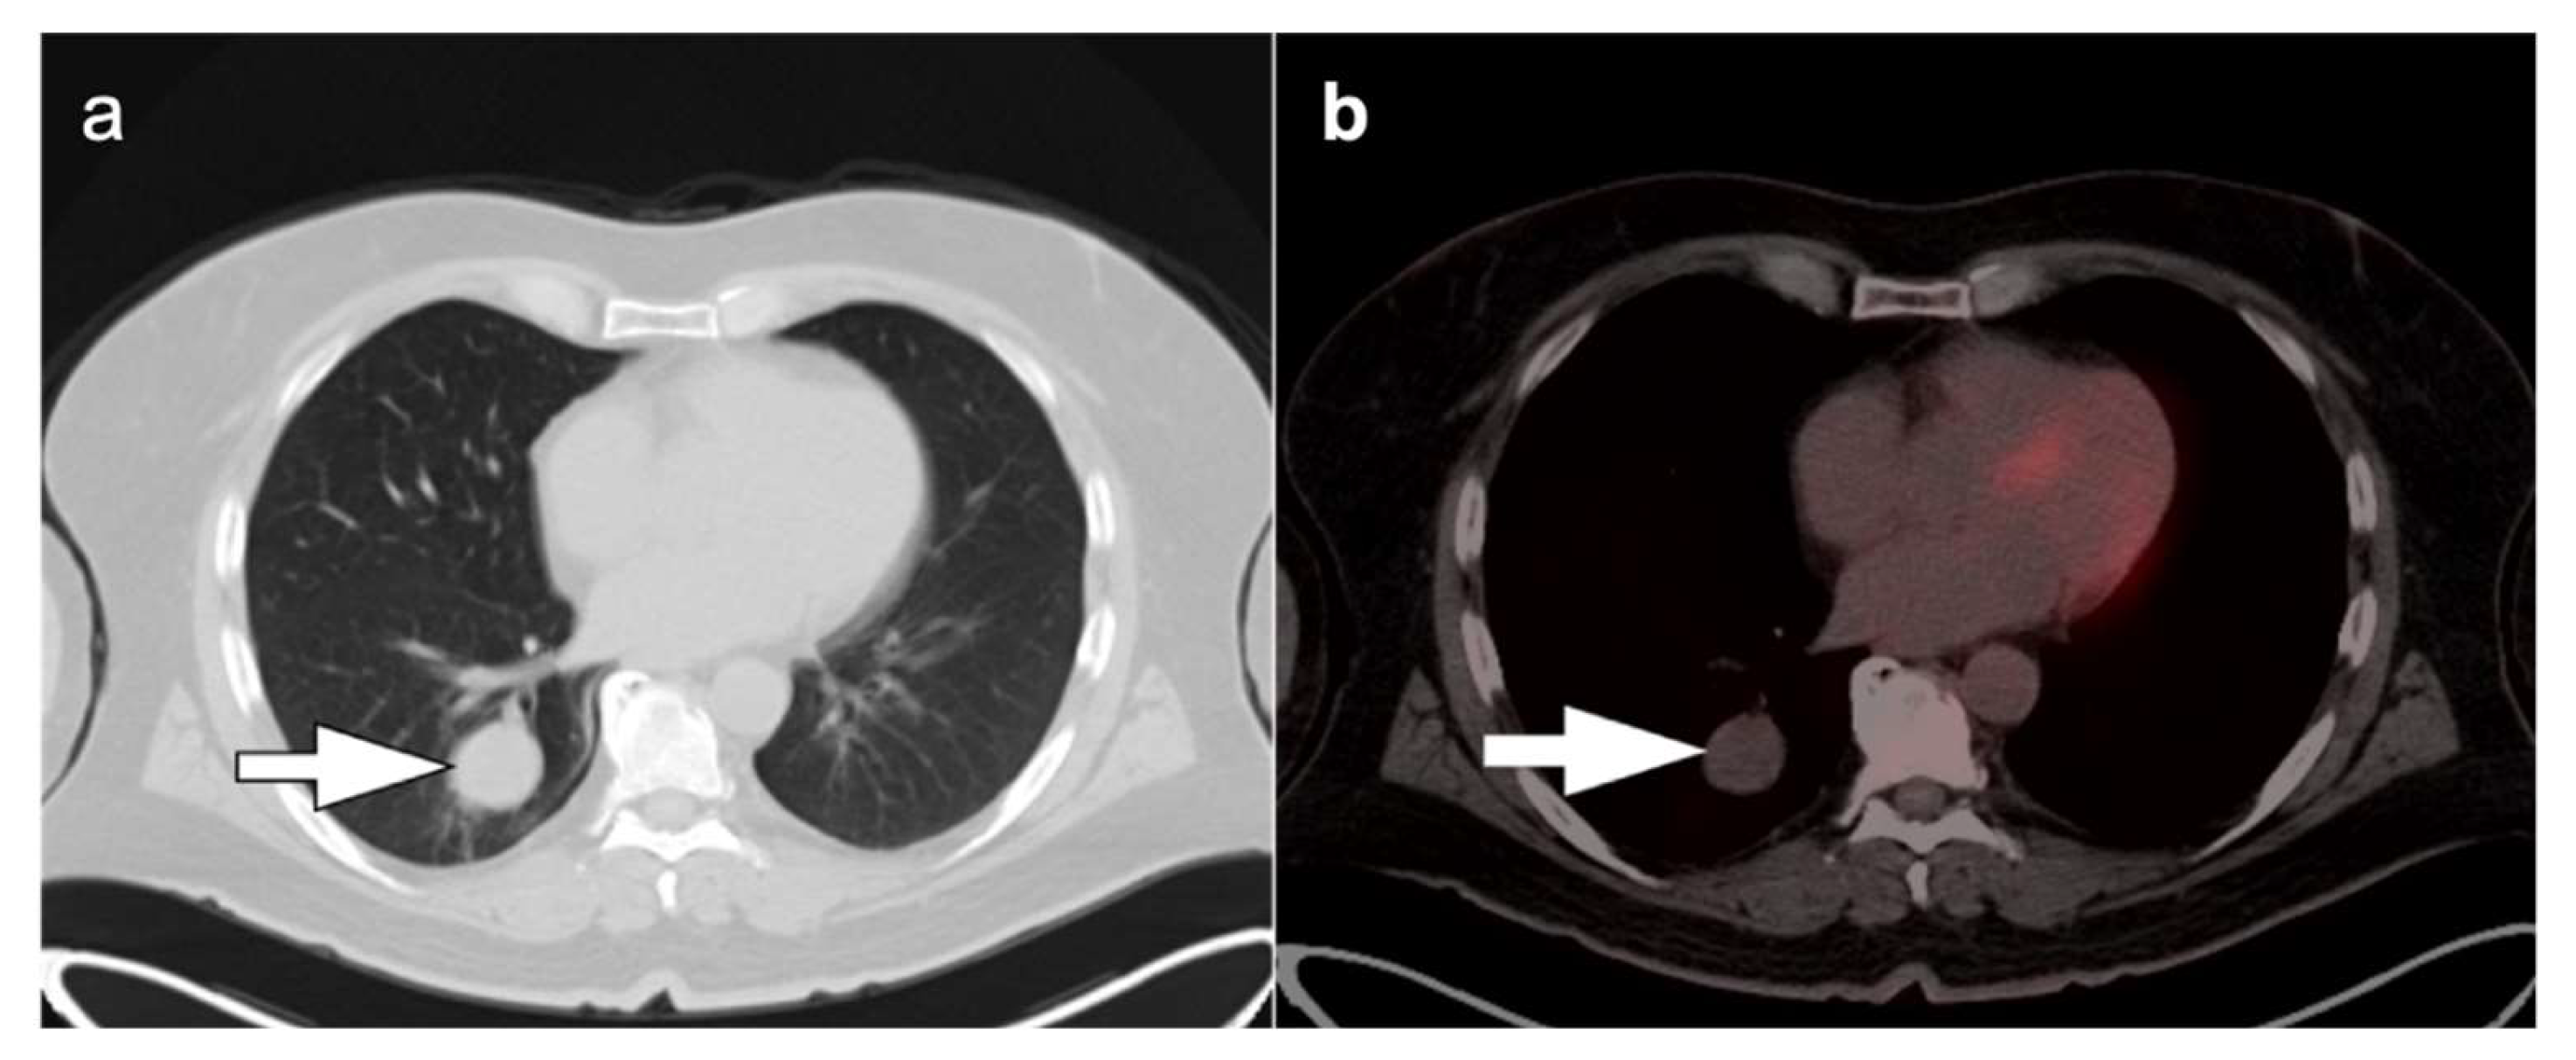

2.2. Evaluation of Solitary Pulmonary Nodules

A solitary pulmonary nodule (SPN) is defined as a single round/oval lesion which is less than 3 cm in size surrounded by lung parenchyma and without associated collapse of the distal lung or lymphadenopathy [15]. Early-stage lung cancer presents as a solitary pulmonary nodule in many patients. However, SPNs are very common, affecting up to 0.1–0.2% of the adult population, and are more common in areas of endemic fungal disease or in older patients. SPNs can be detected incidentally or as a part of screening with low-dose chest computed tomography (LDCT). It is important to establish the nature of SPNs and determine whether they are benign or malignant, though this is not always feasible with conventional CT alone. LDCT nodule screening has been shown to reduce mortality resulting from lung cancer by 20% [16]. Currently, annual screening for lung cancer is recommended with LDCT in adults aged 55–80 years with a 30-year history of smoking who currently smoke or have quit smoking within the last 15 years [17,18]. However, 96% of the nodules detected on screening LDCT are non-malignant and any further evaluation of these nodules adds to the cost and procedure-related complications [19].

FDG PET-CT is shown to be useful in the assessment of solitary pulmonary nodules >8 mm in diameter and is advised in patients who are at low or moderate risk for malignancy (5–20% and 20–80% of all patients with an SPN, respectively), and depending on their radiological characteristics. In addition, FDG PET-CT could benefit patients at high risk for SPN malignancy, by defining the local extent of the lesion and identified regional nodal spread or distant metastases [21]. CT is an excellent imaging modality in the evaluation of SPN, due to its very high sensitivity. However, the specificity of CT is limited. The introduction of FDG PET-CT imaging into clinical practice has had a positive impact on diagnostic specificity in patients presenting with SPNs, because it provides functional as well as anatomical data [22]. FDG PET-CT parameters that are considered suspicious for include a SUVmax of >2.5, metabolic activity greater than that of mediastinal blood pool, or any visually appreciable metabolic activity greater than background lung parenchyma for a lesion <1 cm in diameter [23]. These parameters have the same likelihood of malignancy as recognition of growth of a nodule in a time frame suspicious for lung cancer on CT.

A number of pitfalls can be a hindrance in the assessment of SPNs with FDG PET-CT including inflammatory conditions or infections such as bacterial or fungal infections; and granulomatous entities such as tuberculosis, sarcoidosis, and histoplasmosis, all of which exhibit increased metabolic activity [12,24]. Additionally, FDG PET-CT can result in false-negative studies due to limited spatial resolution of PET cameras, resulting in partial volume effects that limit characterization of very small nodules. Additional causes of false-negative scans are lepidic-type adenocarcinoma (which may be low in metabolic activity), typical bronchial carcinoid tumors, and metastatic disease from tumors that may be low in metabolic activity (such as renal cell carcinoma, some lower grade sarcomas, and some testicular cancers (Figure 7). As such, a lung nodule that is not hypermetabolic on FDG PET-CT must nonetheless be followed by CT according to conventional Fleischner criteria.